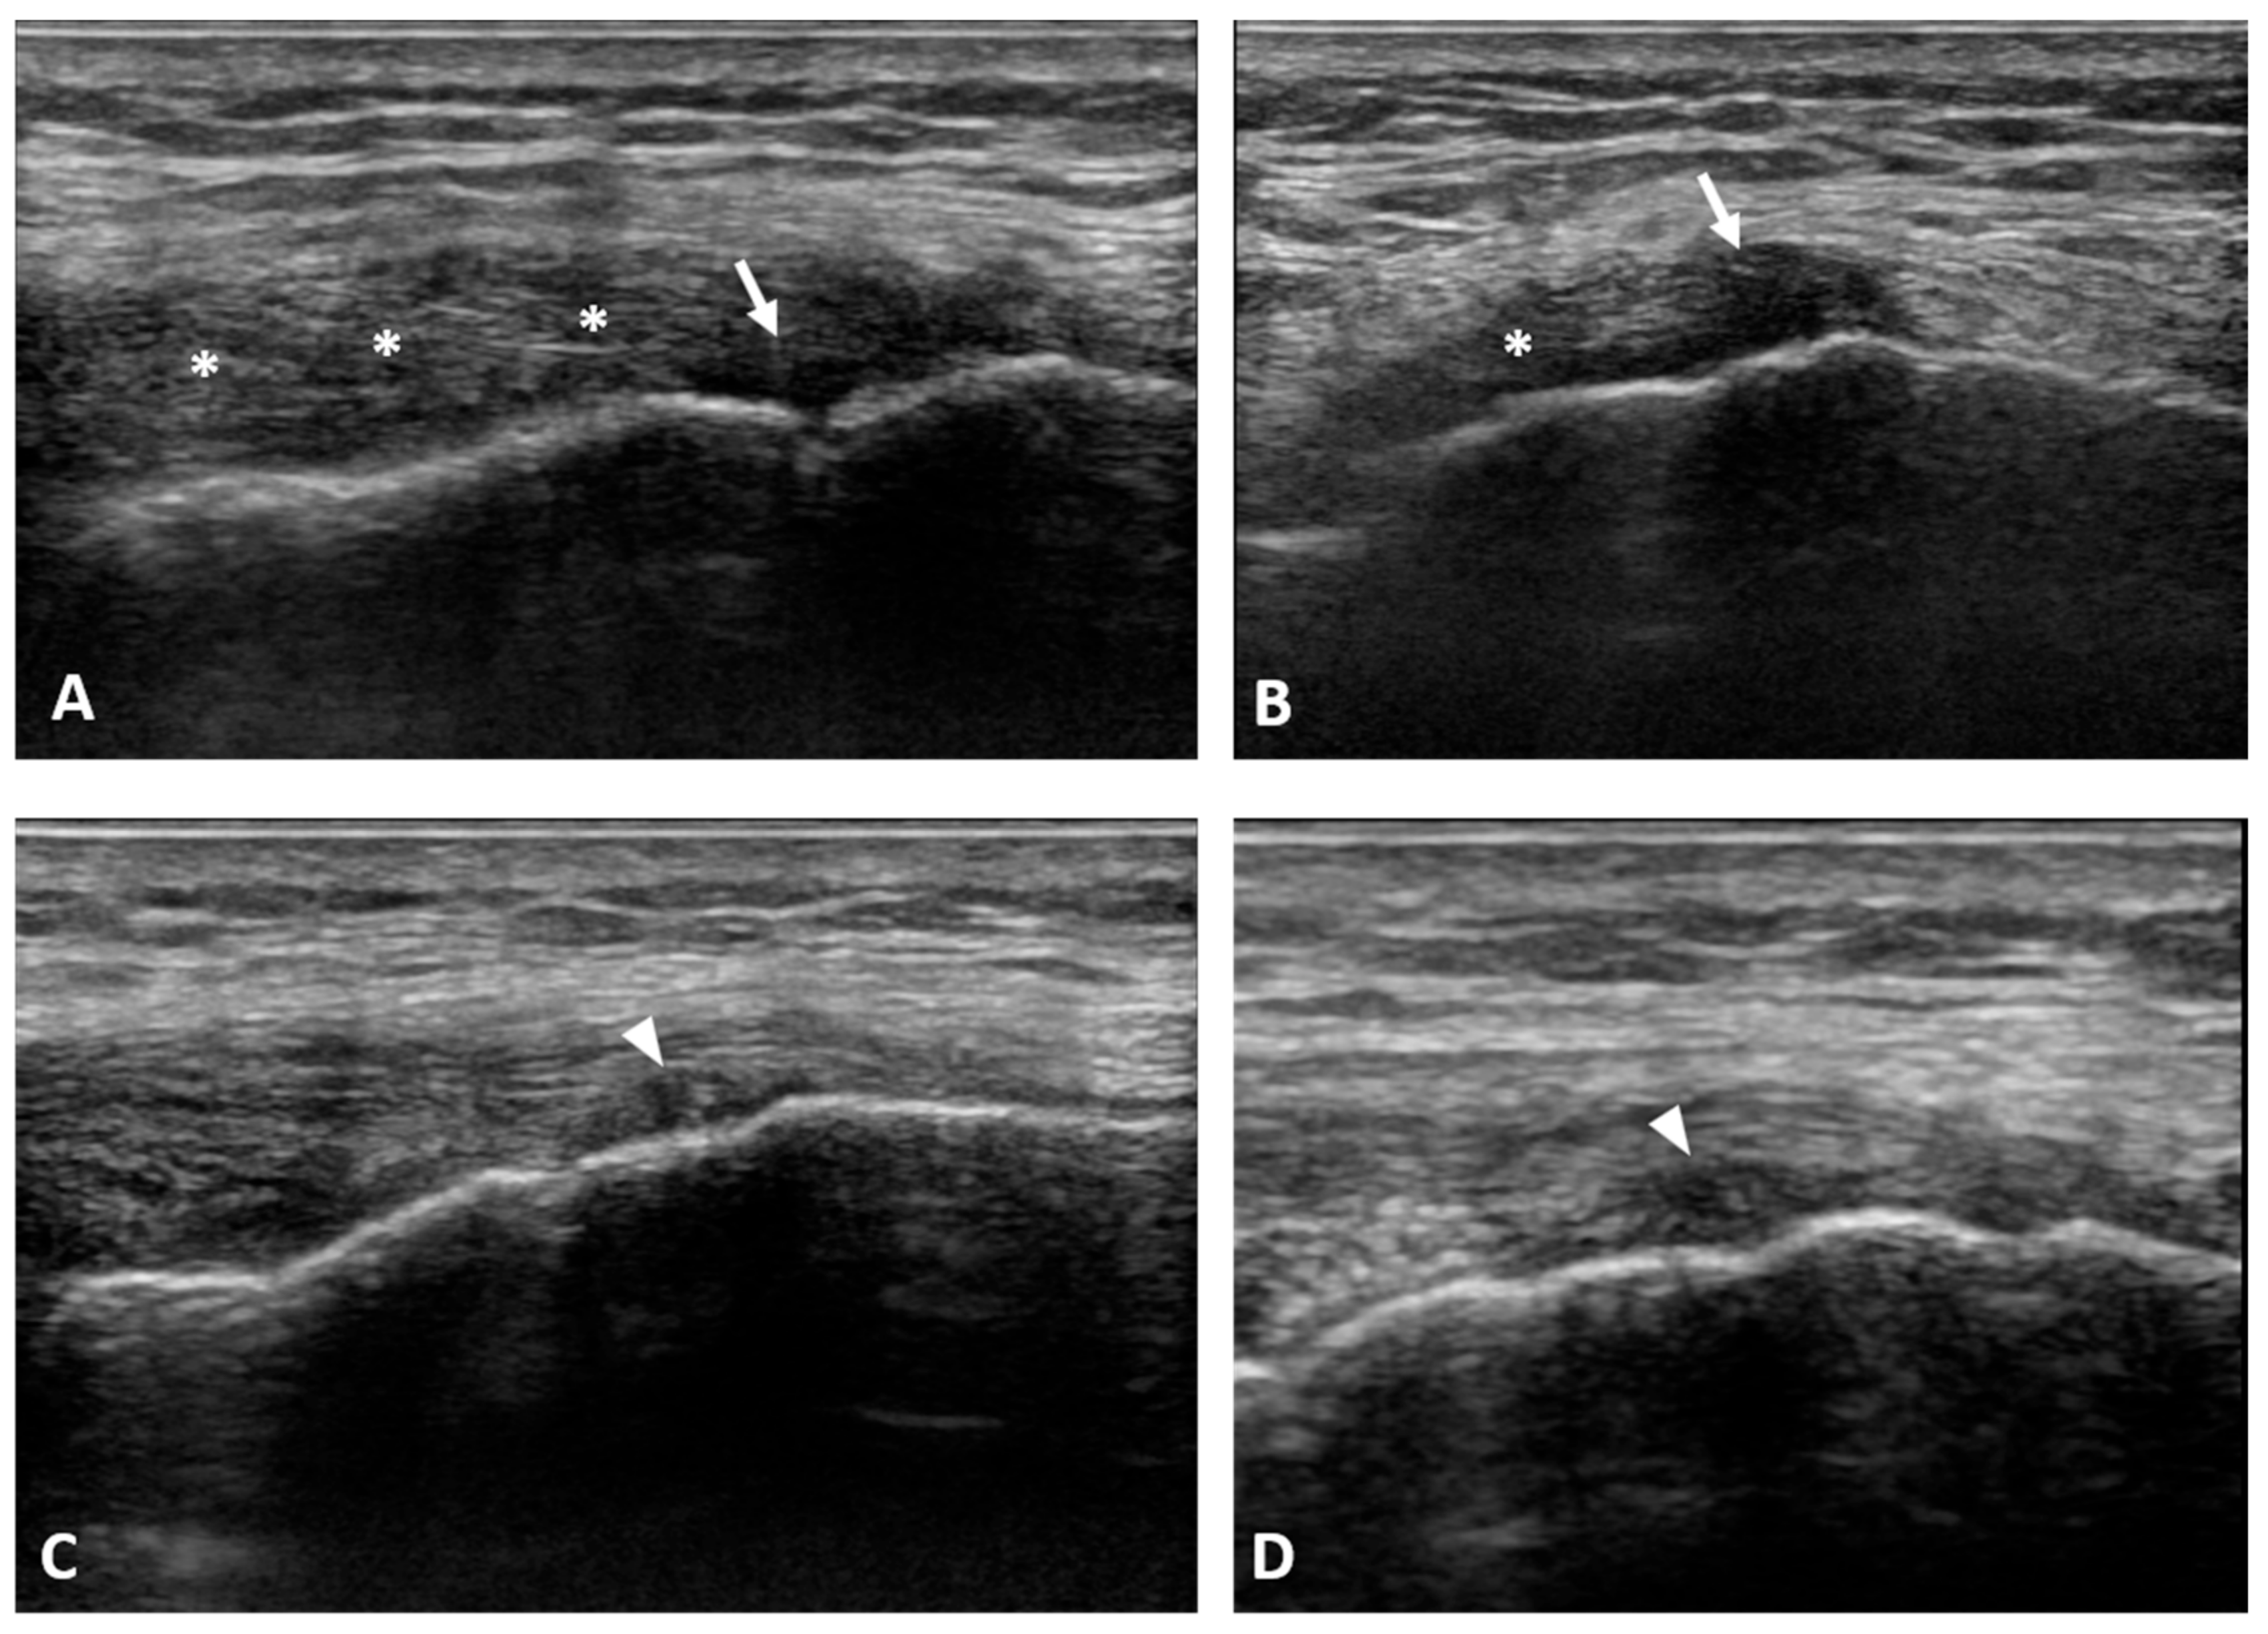

Left-knee magnetic resonance imaging (MRI) from the previous year showed low-grade patella-femoral chondropathy and initial femorotibial osteoarthritis. Physical examination revealed bilateral high and externally rotated patellae. Pain on palpation along the medial collateral ligament with a positive valgus stress test on the left knee was associated with slight atrophy of the left quadricep femoris muscle. US examination at the painful area revealed a thickened and hypoechoic MCL ligament at its femoral insertion with a focal area of lesion at the deep fibers (Figure 1A,B).

Figure 1.

The pre-treatment ultrasound (US) examination at the painful area revealed a thickened and hypoechoic MCL ligament at its proximal (femoral) insertion (asterisks) with a focal area of the lesion (arrows) at the deep fibers (A,B). At 1-month follow-up the US examination showed an initial deposition of “newly formed tissue” at the site of previous injury of the proximal MCL insertion (arrowheads), with an initial reduction in MCL thickness (C,D).

At the 1-month follow-up visit, a clinical and ultrasonographic evaluation was performed. Patient reported a complete resolution of knee pain (VAS 0). The US examination of MCL of the affected knee showed an initial deposition of “newly formed tissue” at the site of previous injury of the proximal MCL insertion. Moreover, a reduction in MCL thickness together with an improvement in echostructure was observed (Figure 1C,D). Such findings were associated with an improvement in knee function with the resumption of regular daily activity.

The clinical evaluation at 4 months post treatment revealed the continued complete absence of pain (VAS 0) with resumption of regular sports activities (walking, jogging) without any symptoms. Moreover, the US examination of the MCL showed a thinner ligament at the femoral insertion, with a clear improvement in echostructure (Figure 2).